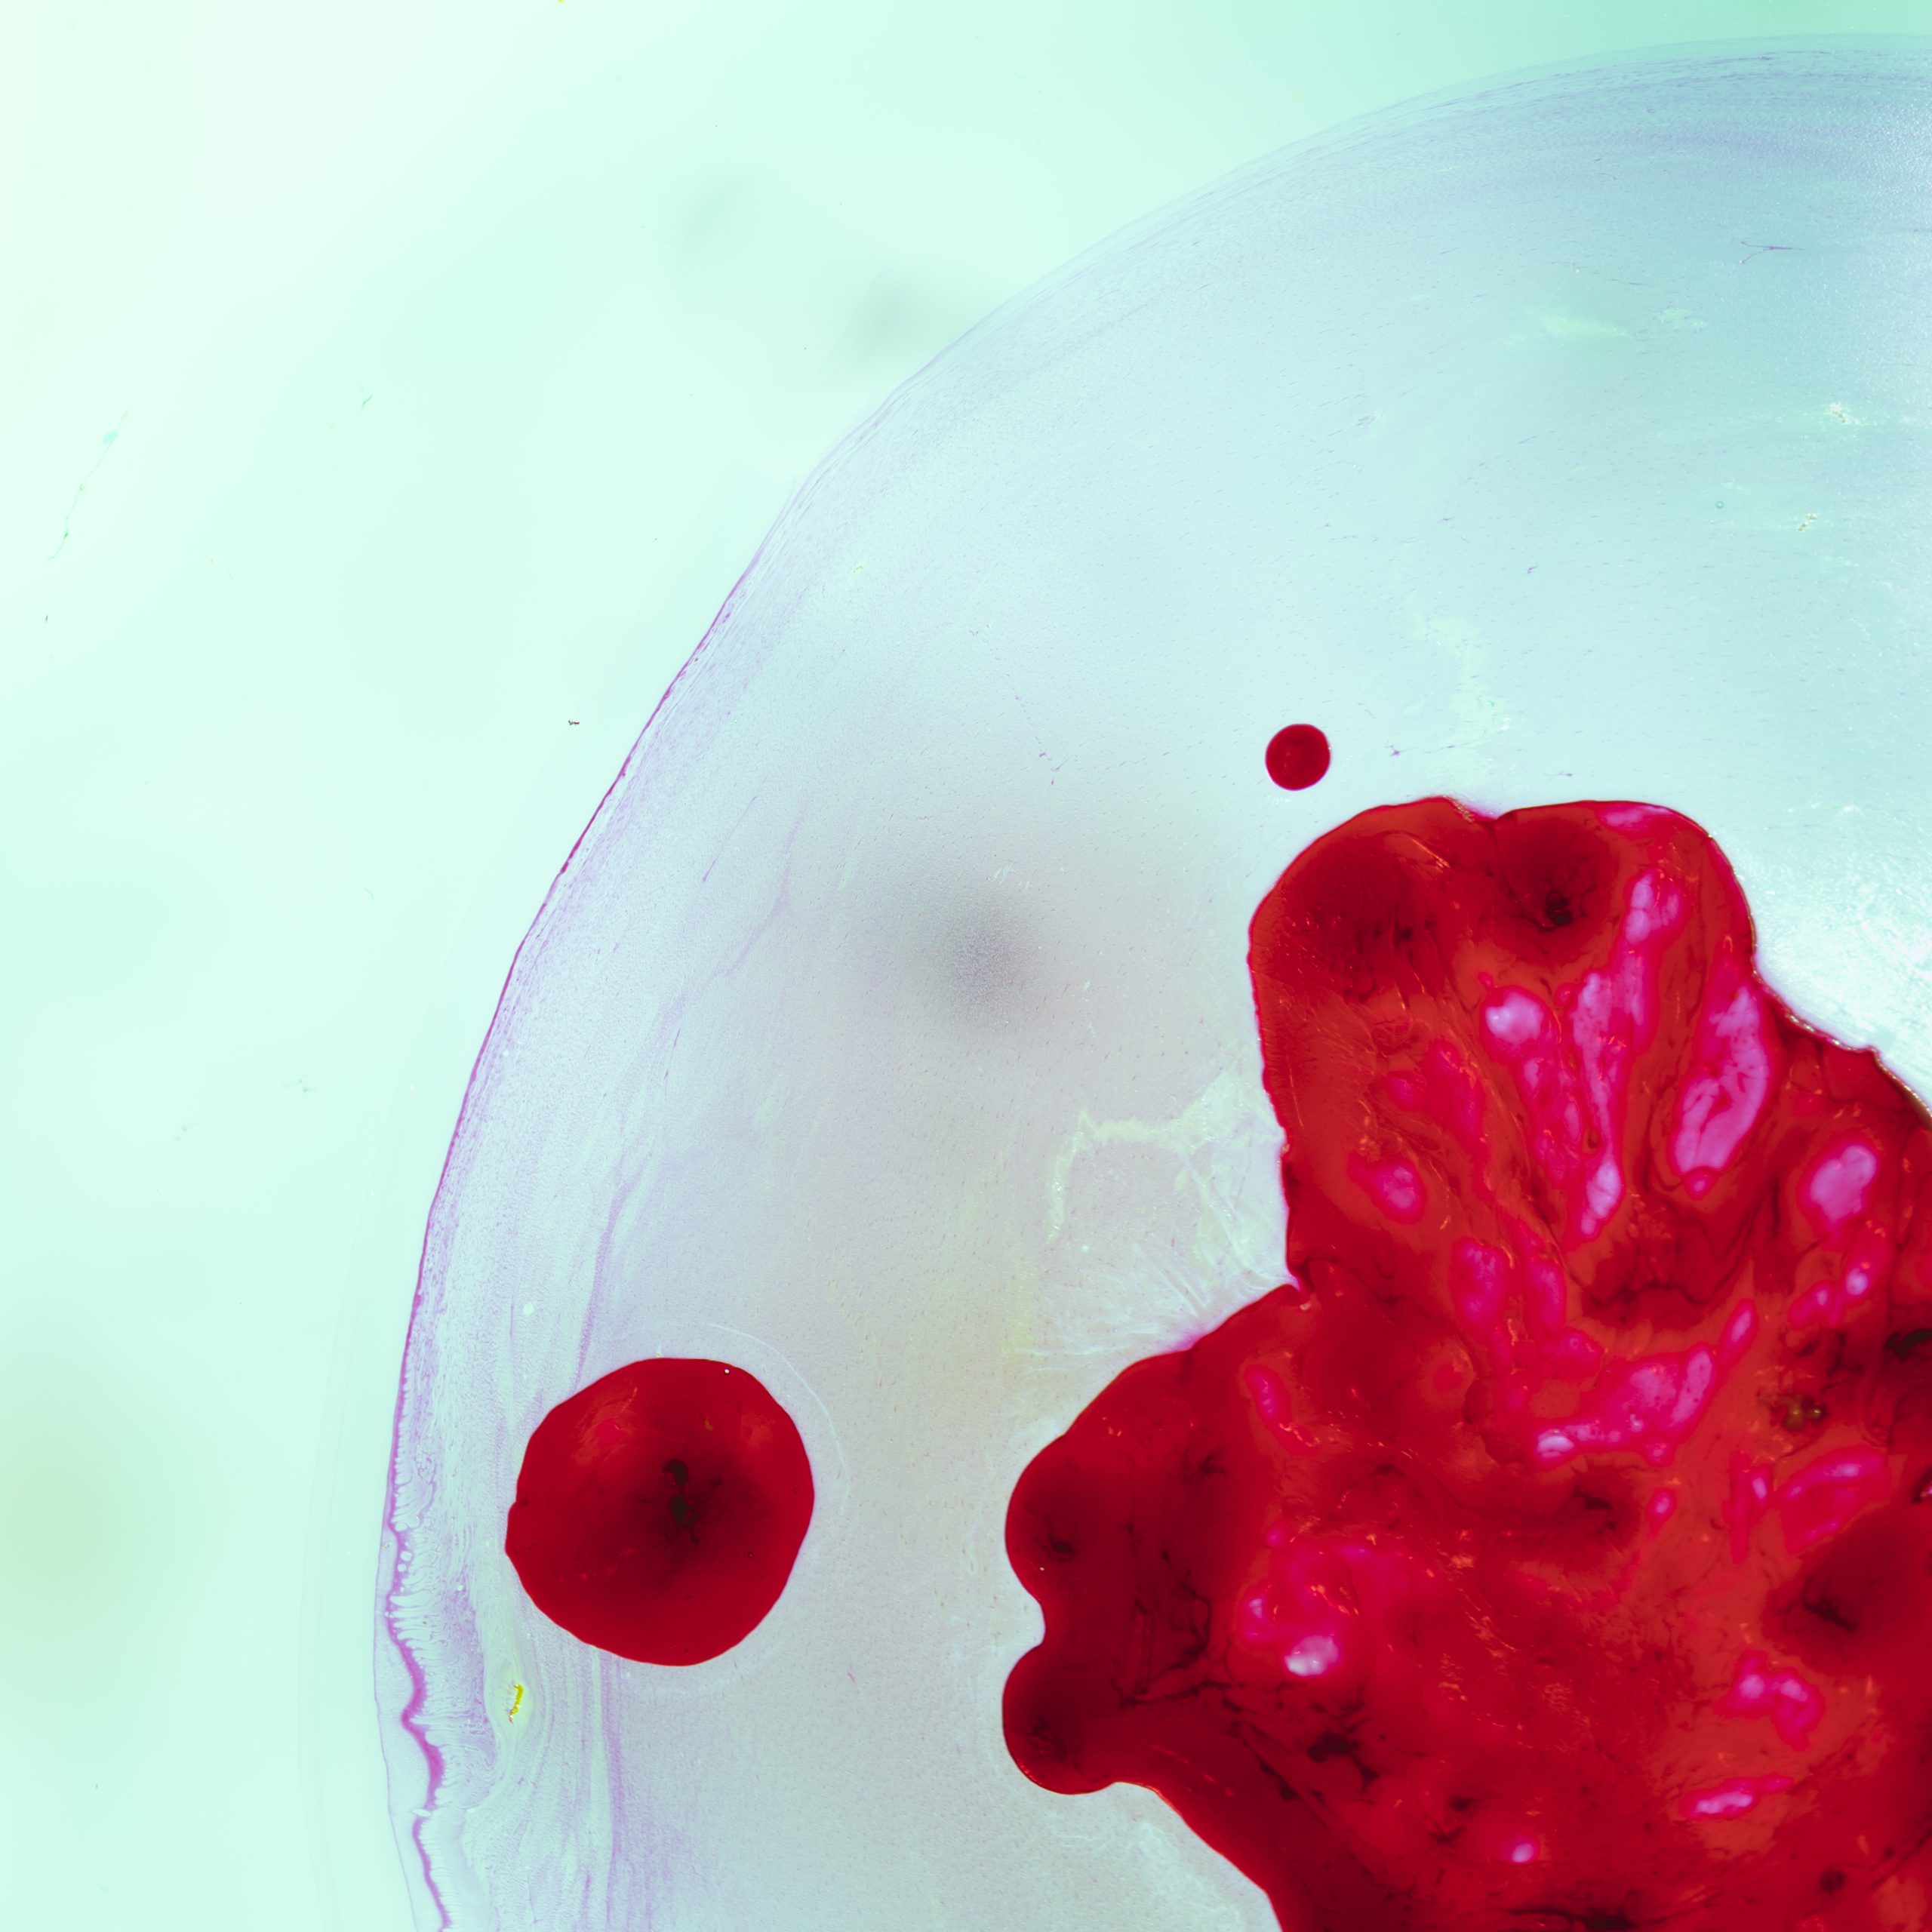

Patients with hemophilia typically present with spontaneous bleeding into joints (hemarthrosis), prolonged bleeding after minor cuts, and easy bruising. Common clinical signs include:

Patients often present with spontaneous hemarthrosis (bleeding into joints), prolonged bleeding after minor injuries or surgeries, deep muscle hematomas, frequent nosebleeds, and easy bruising. Laboratory diagnosis starts with a prolonged activated partial thromboplastin time (aPTT). Specific factor assays then quantify factor VIII or IX activity to determine severity. Genetic testing identifies the exact mutation in the F8 or F9 gene, which guides counseling and may influence treatment choices, especially when inhibitors are present.